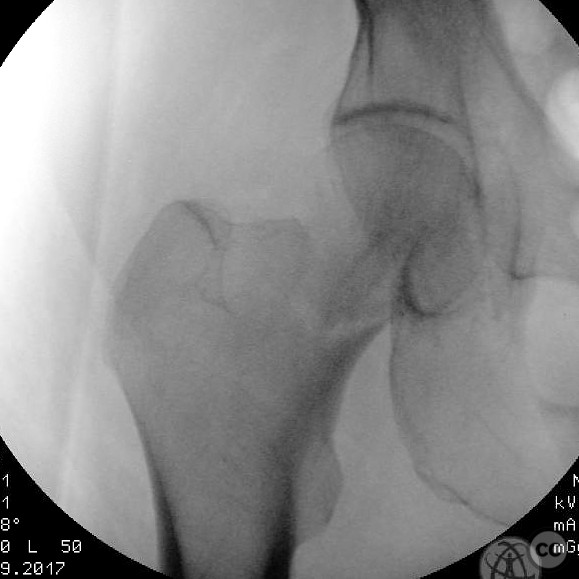

Clinical and radiological findings:  A 62-year-old male presented following a fall from standing height, resulting in a displaced subcapital femoral neck fracture. The patient has a complex medical history including substance abuse (methamphetamine and cocaine), cirrhosis, diabetes, and open draining foot wounds. Radiographs confirmed a displaced femoral neck fracture, classified as AO/OTA 31-B2.

Patient positioning:  The patient was positioned supine on a fracture table to facilitate closed reduction and percutaneous fixation under fluoroscopic guidance.

Anatomical surgical approach:  A percutaneous approach was utilized, involving small stab incisions for the insertion of guide wires and cannulated screws. Fluoroscopic imaging was employed to ensure proper alignment and fixation.